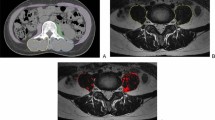

MRI is the gold standard for muscle assessment [88,89,90]. In addition, MRI is non-invasive and extremely reliable technique. MRI allows high-contrast distinction of soft tissue components (muscle, fat mass, and water) depending on anatomical compartment molecular characteristics. MRI may identify changes in muscle composition, such as muscle disruption, edema, or intramuscular adipose tissue (myosteatosis) and fibrosis (myofibrosis), as well as other biochemical indicators related to muscle quality. Intramuscular adipose tissue is made up of intermuscular and intramuscular fat. Anatomical T1- and T2-weighted sequences are often employed to assess muscle fat content. Anatomical imaging can measure CSA and muscle volume. These measures may identify hypertrophy or atrophy [91, 92]. Semiquantitative MRI muscle atrophy and fat infiltration methods have been published. The semiquantitative CT ratings may also apply to MRI (Fig. 3). Based on the amount of intramuscular fat visible on CT scans, Goutallier and colleagues were the first to describe fatty infiltration grades of the shoulder rotator cuff muscles on a five-point scale (0 = normal muscle; 1 = the muscle contains some fatty streaks; 2 = the fatty infiltration is important, but there is still more muscle than fat; 3 = there is as much fat as muscle; 4 = more fat than muscle is present) [93]. Modifications of the Goutallier classification to evaluate muscle volume and fat infiltration have recently been suggested for MRI with better reliability [94,95,96,97,98] (Fig. 4).

The modified Goutallier classification [93] of fatty infiltration on MRI on a 4-point scale: 0 = normal; completely normal muscle, without any fatty streak; 1 = mild; muscle contains some fatty streaks; 2 = moderate; fatty infiltration is important, but there is more muscle than fat; 3 = severe; more fat than muscle is present

An MRI sequence including a region of interest (ROI) may be used to segment muscles and fat to quantify muscle and fat volume. Another study recommended measuring muscle volume from a single leg section to save money and effort. Selected anatomical landmarks' CSA have been found to be good surrogates for total skeletal muscle amount [113]. These findings are consistent with those of Yang and colleagues [114]. The authors predicted that a single MRI segment may represent the whole thigh. Other studies have linked CSA to quadriceps, hamstrings, and adductors [115, 116]. Because CSA may be recorded in a single slice rather than segmenting the whole thigh muscle volume, this can drastically reduce costs, scan time, and post-processing time. Semiquantitative evaluations have been proven to be less reliable than CSA measurements and advanced quantitative segmentation algorithms in 2D or 3D [117, 118]. Manual muscle segmentation is repeatable yet time demanding, limiting its utility in large-scale research. Muscle and other tissues have recently been quantified utilizing semiautomatic and automated threshold changes in pixels/voxels [119, 120]. Our research uses the open-source program Horos (version 3.3.6 for macOS 10.11 +), which is based on OsiriX and other open-source technologies, to semiautomatically segment the quadriceps muscle CSA and pixel-based intensity (PI). Dedicated software like Horos allows 3D segmentation with QMV reconstruction and differentiation of skeletal muscle mass and adipose tissue volume (Fig. 5).

Skeletal muscle mass and adipose tissue volume reconstruction (software Horos) on MRI images. The quadriceps muscle volume reconstruction is based on the selection of the T2w dataset, selection of the command to generate the “Region of Interest,” insertion of the threshold interval, selection of the parameter “3D Growing region,” so that all the slices are considered, and application of the command “Brush ROI” to obtain a complete segmentation